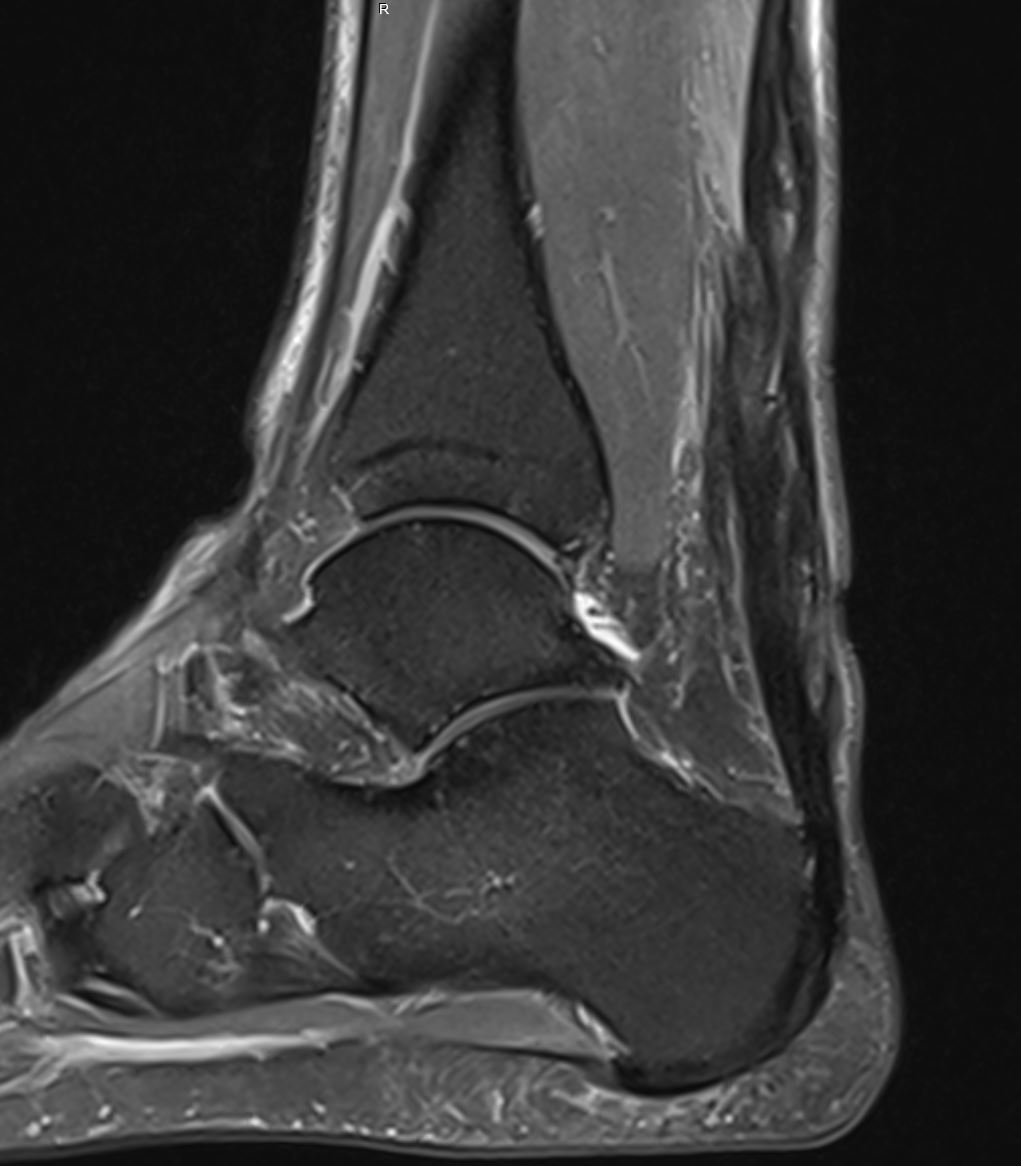

Home Schwerpunkte Krankheitsbilder Achillessehnenruptur Achillessehnenrutpur 8 Wochen nach Operation bei Achillessehnenriss Achillessehnenrutpur 8 Wochen nach Operation bei Achillessehnenriss Achillessehnenrutpur 8 Wochen nach Operation bei Achillessehnenriss